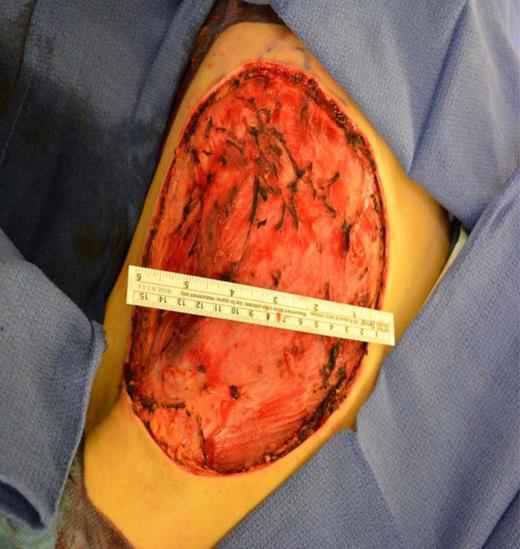

A left mastectomy was performed. The excised mass was 20 × 20 × 25 cm in size (Fig. 3). The tumor did not appear grossly to be invading the chest wall. The pectoralis fascia was free of tumor invasion (Fig. 4). The left chest wall defect was covered temporarily with dual layers dermal regeneration template consists of thin outer layer of silicone and thick inner matrix layer of pure bovine collagen and glycosaminoglycan (INTEGRA®) in the same operation, and subsequently replaced with split thickness skin graft 5 weeks later (Fig. 5). Final histological examination was consistent with phyllodes tumor with low-grade malignant features with negative margins (Fig. 6).